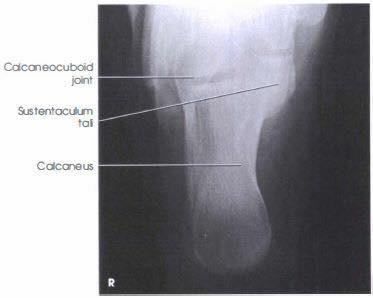

Las radiografías, generalmente llamadas rayos X, producen imágenes como sombras de huesos y ciertos órganos y tejidos. Las radiografías son muy buenas para detectar problemas óseos. Pueden mostrar algunos órganos y tejidos blandos; sin embargo, la MRI y la CT suelen crear mejores imágenes de los mismos. Aun así, las radiografías son rápidas, fáciles de obtener y menos costosas que los otros estudios, por lo que se pueden usar para obtener información rápidamente.

Un tubo especial dentro de la máquina de rayos X emite un haz de radiación controlada. Los tejidos del cuerpo absorben o bloquean la radiación en diferentes grados. Los tejidos densos como los huesos bloquean la mayor parte de la radiación, pero los tejidos blandos, como la grasa o los músculos, bloquean menos radiación. Después de pasar por el cuerpo, el haz alcanza una pieza de un fragmento de película o un detector especial. Los tejidos que bloquean altas cantidades de radiación, como los huesos, aparecen como áreas blancas en un fondo negro. Los tejidos blandos bloquean menos radiación y aparecen en tonos de gris. Los órganos que contienen principalmente aire (como los pulmones) aparecen en negro. Los tumores son por lo general más densos que el tejido que los rodea, por lo que suelen verse en tonos grises más claros.